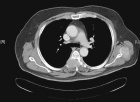

D.C. - 63 year old male with back pain and paresthesias across the chest wall

Zoom image: Radiological image Radiological image.